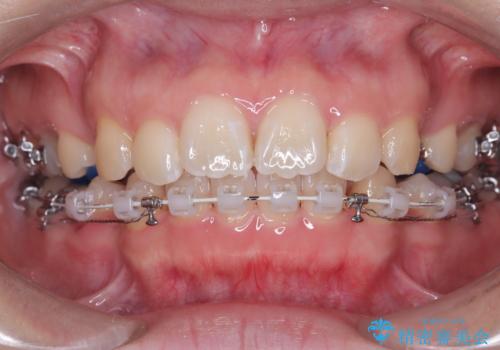

目立たない矯正で口元の突出感を解消

- 口元が出ている(突出している)ことを気にされて来院されました。精密な検査の結果、前歯を大きく後退させるスペースが必要と診断。患者様の**「前歯を下げたい」という強いご要望に応えるため、上下左右の第一小臼歯を抜歯し、そのスペースを利用して前歯を奥へ移動させる治療計画を立案しました。また、人目を気にせず治療できるよう、上顎に裏側矯正、下顎に表側矯正を組み合わせたハーフリンガル矯正**を提案しました。

今回の矯正治療では、前歯を大きく後退させるスペースを確保するため、計画通り上下左右の第一小臼歯を抜歯しました。装置には、上顎には目立たない裏側矯正(舌側矯正)を、下顎には透明な審美ブラケットを使用するハーフリンガル矯正を採用しました。抜歯によってできたスペースを最大限に活用し、前歯を効率よく後方へ移動。治療の結果、口元の突出感が大幅に解消され、Eライン(横顔の美しさの基準)も改善しました。人目を気にすることなく治療を完遂し、自信の持てる美しい横顔を獲得していただけました。